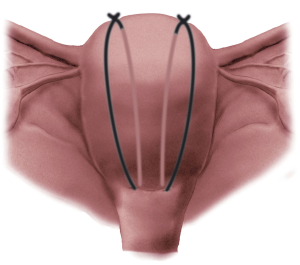

55f28d9715bbdff6.PK_2a_1

f559648e926da6e6.PK_3a_1